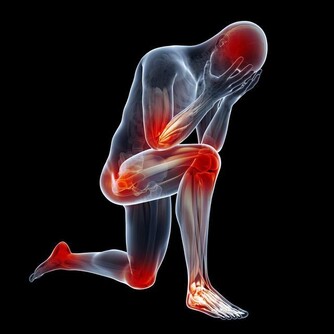

6. 早期飢餓導致虛弱、肌肉損失和脫髮

斷食超過48小時後,可能有一些相當嚴重的後果。

比如虛弱和疲勞,這可能導致你暈倒;肌肉損失;

骨密度降低,導致骨骼非常脆弱;

心臟肌肉減弱引起的心臟問題;血壓降低;

潰瘍以及由於循環不暢而出現的並發症;

感覺很冷;嚴重脫水導致腎衰竭;脫髮嚴重。